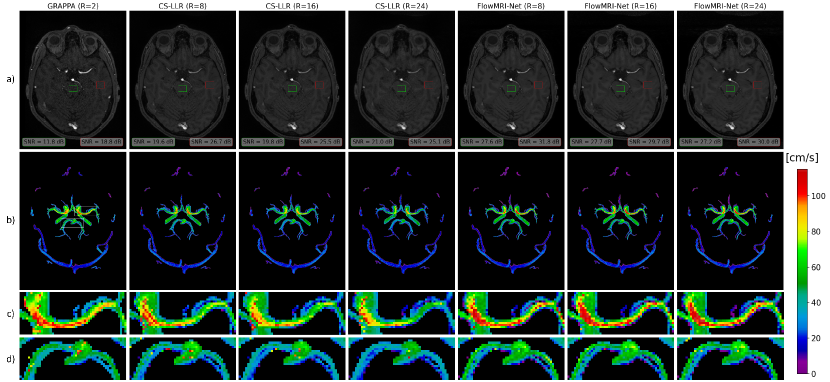

Reconstructions of a cerebrovascular acquisition at undersampling factors R=8,16, and 24 can be seen in Fig. 5. Visually, the image magnitude of the frame-by-frame reconstructed GRAPPA reference is noisier than the CS-LLR and FlowMRI-Net reconstruction at higher undersampling factors, which is reflected by the lower SNR, particularly in the brain stem furthest away from the coils. Undersampling artifacts appear in the image magnitude for the CS-LLR reconstruction at R=24, with visible underestimation of velocity magnitudes at all undersampling factors, particularly in the left and right internal carotid arteries (ICA) and middle cerebral arteries (MCA). Contrarily, the proposed FlowMRI-Net demonstrates better agreement of velocity magnitudes with the reference GRAPPA reconstruction, even up to the highest undersampling factor (R=24). These observations extend to the peak velocity curves for the left and right MCA and ICA, as seen in Fig. 6, where FlowMRI-Net shows superior agreement with the GRAPPA reconstruction compared to CS-LLR, which tends to underestimate peak velocity magnitudes. CS-LLR underestimates and FlowMRI-Net overestimates the peak velocity in the left and right PCA at all undersampling factors.

For cerebrovascular reconstructions, using a two-fold GRAPPA reconstruction as reference, we showed that FlowMRI-Net resulted in improved noise reduction in images magnitudes compared to CS-LLR (Fig. 5), whilst accurately capturing peak velocity magnitudes in the left and right MCA and ICA, even up to an undersampling factor of R=24 (Fig. 6). The velocities in the left and right PCA remain challenging to recover for both CS-LLR and FlowMRI-Net even at R=8 due to the relatively small vessel diameter (2.7 0.04 mm for the P2 segment that we considered) [62] compared to the spatial acquisition resolution of 0.8 mm 0.8 mm 0.8 mm. The CS-like k-space sampling implemented on the Siemens system for the cerebrovascular acquisitions was not optimized and may be suboptimal for FlowMRI-Net. In brief, the sampling pattern has non-random patterns that cause higher lateral peaks in the corresponding point-spread function (i.e. higher coherence) compared to truly pseudo-random sampling, resulting in structured undersampling artifacts that are undesirable in our context [11]. Moreover, the corners of k-space, which are less critical, were sampled relatively densely; a proper elliptical shutter can increase imaging efficiency. Furthermore, it is currently unclear whether incoherent/complementary sampling between velocity-encodings is desirable for FlowMRI-Net reconstructions. Namely, such incoherence may be beneficial when exploiting redundancies between velocity encodings for the joint reconstruction [32]. On the other hand, coherence may be beneficial because any undersampling artifacts that remain after reconstruction would be the same for the velocity encodings and hence would disappear when computing phase differences. Future work should investigate a more optimal sampling pattern, possibly incorporating it in the optimization loop for an anatomy-specific sampling [63, 64]. Finally, a larger cohort including patients should be considered for further validation and proof of generalizability to pathological flow dynamics, such as an intracranial aneurysm, should be investigated.